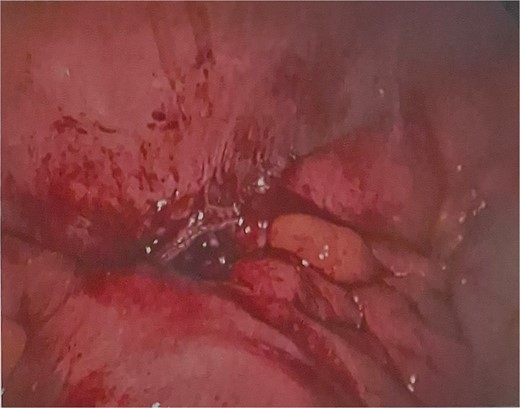

He was brought to theatre for a combined laparoscopic appendicectomy, drainage of peri-appendiceal abscess and cholecystectomy with intraoperative cholangiogram. Intraoperative findings included a 2 cm peri-appendiceal abscess cavity (Fig. 3) in keeping with pre-operative imaging. However, the gallbladder was gangrenous with a possible microperforation sealed by omentum (Fig. 4). Based on the intraoperative appearance, it was difficult to ascertain whether the abscess was due to primary appendicitis or whether the abscess was seeded from the cholecystitis and the appendix had become involved collaterally.